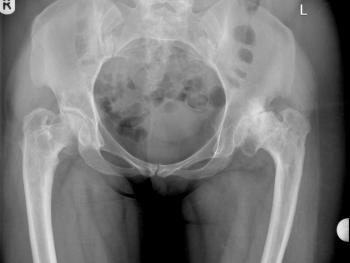

Clinical cases: variations of Exeter stem size and offset copes with almost all abnormal anatomies.

Figure 7 & Figure 8: DDH case with bowed femur and over-riding GT.

Figure 9 & Figure 10: DDH case – small socket – 40/22mm required. Leg length restored. Modularity of head sizes and offsets allows accurate restoration of leg length and offset.